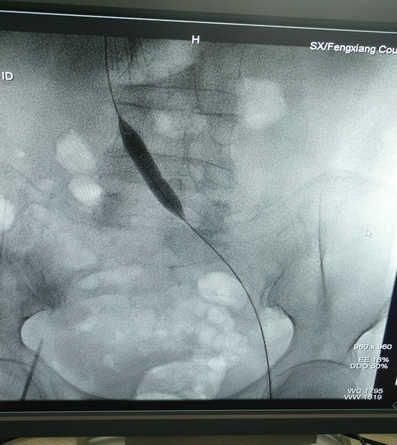

患者辛某,两月前左腿肿胀来我院就诊,B超检查发现左下肢深静脉血栓,经下腔静脉滤器植入术标准抗凝治疗后,患肢肿胀明显改善,两月后复查超声,左下肢深静脉内血栓基本消失,但左腿肿胀仍时轻时重。近期又在我院住院治疗,经左下肢顺行造影发现左侧髂静脉完全闭塞。经由交大一附院刘亚民教授会诊后,诊断为左侧髂静脉压迫综合症。

6月30日晚8时,在刘亚民教授的精心指导下,介入科李渊博主治医师与科室医护人员为该患者实施了血管开通、球囊扩张成形及支架置入术,术后造影,左侧髂静脉通畅,患者安全返回病房。